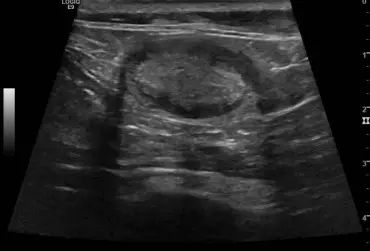

Rzekomołożyskowy przerost błony śluzowej macicy u suk w badaniu ultrasonograficznym

Rzekomołożyskowy przerost błony śluzowej macicy jest rzadko występującą formą przerostu endometrium występującą u młodych suk. Opisano przypadek występowania tej formy przerostu u 18-miesięcznej suki rasy flat coated retriever z wieloma nieswoistymi objawami, w tym przedłużającą się cieczką. W badaniu USG wykryto obecność pięciu zmian miejscowych w rogach macicy w postaci hipoechogennej, pogrubiałej błony śluzowej z obecnością ognisk i pasm hiperechogennych prostopadłych do osi długiej macicy oraz nietypową, hiperechogenną warstwę w centrum. Obraz zmian odpowiadał rzekomo łożyskowemu przerostowi endometrium, natomiast obecność hiperechogennej, wewnętrznej warstwy błony śluzowej macicy mogła wynikać z długości czasu trwania estrus. Zastosowano leczenie zachowawcze aglepriston podawanym podskórnie. Zmiany istotnie zmniejszyły się po zakończeniu leczenia, po czterech miesiącach nie były widoczne.